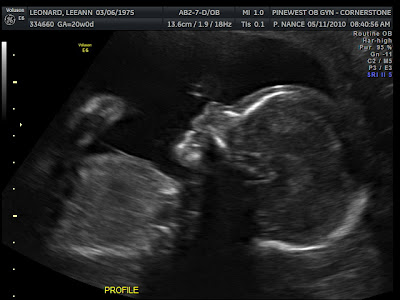

Today was a big day for the Leonard Family. It was the 20 week ultra sound. This is the visit when they measure absolutely everything there is to be measured. If you wanted to find the sex of the baby you could at this time. Ken of course wanted to. I of course wanted it to be a surprise.

Other then that.. I guess this post is just about finished.. Am I forgetting anything????? Ahh yesmeet our Son, Babe Leonard!